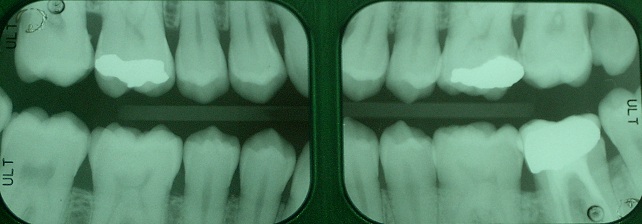

RADIOGRAFIE BITE WING

Le radiografie Bite Wing sono delle normali radiografie endorali che l'odontoiatra utilizza con una speciale tecnica di posizionamento orale in modo da ottenere, con solo due radiogrammi, un quadro diagnostico di primo livello molto esaustivo delle condizioni del paziente e delle patologie in atto nei settori posteriori.

Il grosso vantaggio per il paziente è quello di limitare il tempo di esposizione e la dose, comunque bassissima, di radiazioni assorbita.

Le dosi di radiazioni che si ricevono durante una radiografia endorale, sono normalmente molto basse. Si calcola che la dose annua tollerata per persone che vengono esposte alle radiazioni per ragioni professionali, sia equivalente a quella di circa 8.000 radiografie endorali annue.

Da questo esame si possono trarre numerose informazioni:

- Stato delle corone dentali

- Stato dei restauri conservativi (otturazioni) (2)

- Stato dell'osso

- Presenza di tasche ossee

- Presenza di impianti

- Lesioni cariose primarie (4)

- Lesioni cariose secondarie (3)

- Spicole di pericolosissimo tartaro sottogengivale (1)

- Restauri protesici con margini incongrui (5)